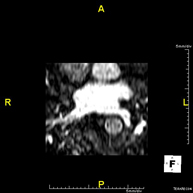

- Renal artery MRI angiography

A non-invasive diagnostic test that involves studying the renal arteries, obtaining high-definition anatomical images using an electromagnetic field and radio waves (with transmitter and receiver). The use of paramagnetic contrast (gadolinium) is essential. However, it is a radiation-free procedure. The quality of the images allows for 2D and 3D reconstructions. This test is recommended, for example, in patients suffering from refractory hypertension that does not respond to processing, in patients with kidney damage in order to obtain a pre-surgical ‘vascular’ map, etc.

A non-invasive diagnostic test that involves studying the abdominal aorta, obtaining high-definition anatomical images using an electromagnetic field and radio waves (with transmitter and receiver). The use of paramagnetic intravenous contrast (gadolinium) is essential. However, it is a radiation-free procedure. The quality of the images allows for 2D and 3D reconstructions. This test is recommended, for example, in patients suffering from refractory hypertension that does not respond to processing, in patients with kidney damage in order to obtain a pre-surgical ‘vascular’ map, etc.